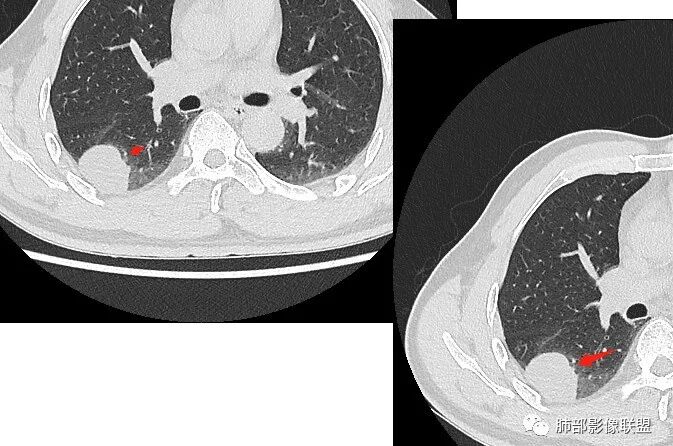

右肺下叶占位,胸膜下,与胸膜关系密切;

密度均匀;糊墙,边缘膨隆为主;

部分血管推移。

这个结节呢?

血管也是稍推移,在边缘,病灶密度均匀,边缘稍收缩;均匀强化;

这两个病灶的密度、强化、形态、边缘、与血管的关系类似;还是一元论吧。

右肺中叶病灶

GGO,与支气管关系密切

这个形态、与支气管关系,与前两个不一致,所以考虑独立炎性病变。